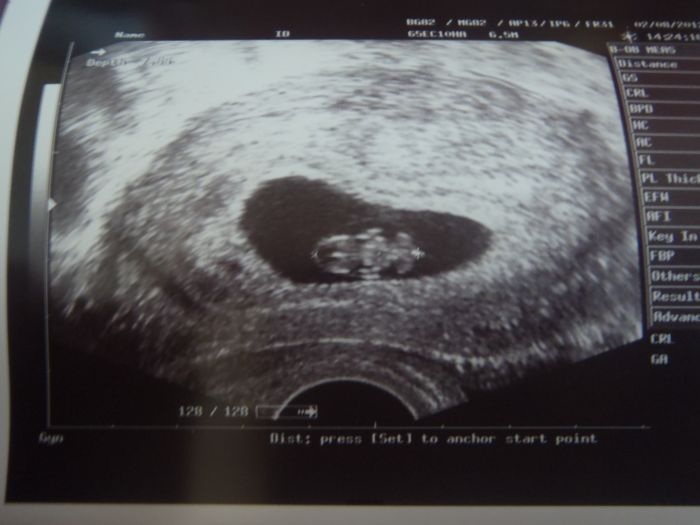

Ahojky těhulky.. Tak já jsem tu prvně,teda v diskuzích :D jinak jsem tady celkem často,na těchto stránkách... TP mám na 7.3.takže jak říkám,mám na to čas si vše pořádně užít :D u mého prvního chlapečka jsem do 4.měsíce nevěděla,že čekám :D to až doktorka :D Tentokrát máme mimi plánovaný , dokonce se podařilo zapadnout hned :D takže radost veliká... jak se cítím??? no ,abych řekla pravdu,je mi hrozne uz cca 14dnu od poceti jen jsem dřív nevěděla důvod,test byl dlouho negativní :( blivno mi je stále,jak mám hlad je to špatný,když se najím víc je to špatný,takže si člověk nevybere :D ale to k těhu patří :D a ja si snad konečně to druhé mimi užiju se vším :D páč takovýhle problémy jsem u malého nezažila :D ať se maminy daří :D na fotečce máme 8 týdnů :D

Lékař mě ujistil, že na migrénu mohu jen paralen či při velkém záchvatu Algifen a následky to mít nebude. Na kontrole jsem byla 5,5 týdne a viděla jsem srdíčko, i foto máme. Další kontrola bude příští týden a rovnou mé krevní testy (Nyní jsme 8+6tt). Už je máte někdo za sebou???